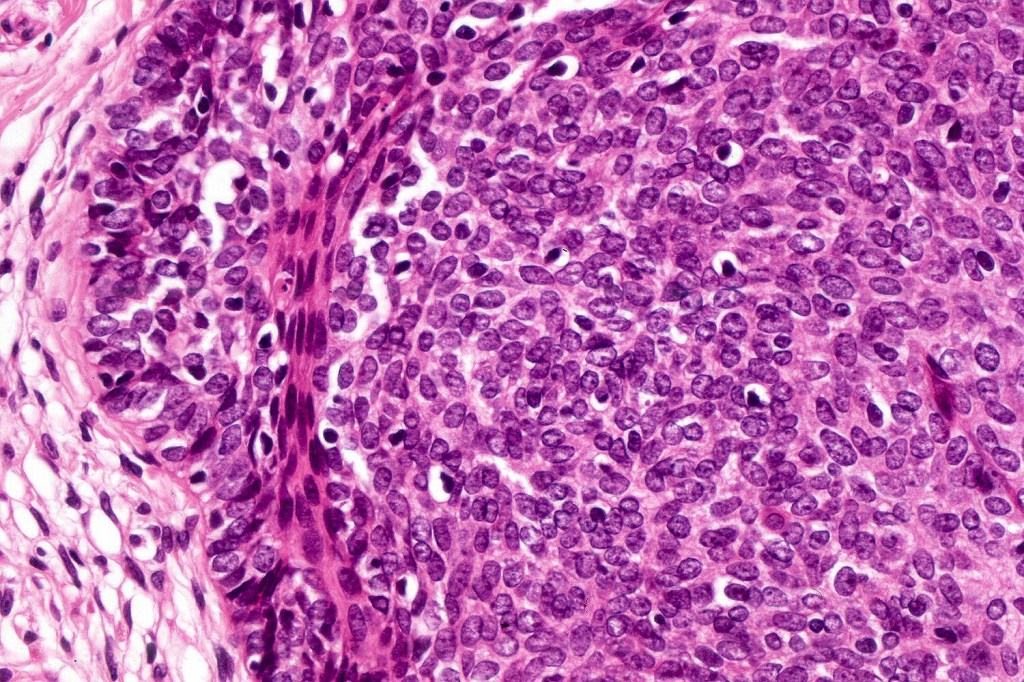

•Variably sized but generally large, basophilic tumor nodules composed of small uniform basaloid cells with minimal cytoplasm

•Variable mitotic activity, can be brisk

•No pleomorphism or abnormal mitoses

•Peripheral palisading but no retraction artifact or stromal mucin deposition